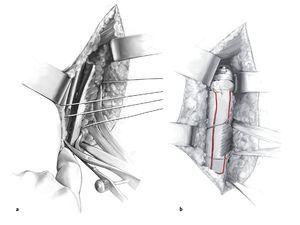

Figura 2 Luxación del húmero proximal con hemiartroplastia in situ: ausencia de tuberosidades y de manguito rotador. Siempre que sea posible, conservar los restos del manguito de los rotadores (el teres minor con frecuencia permanece intacto), y se movilizan los restos de tuberosidades utilizando suturas de tracción. Tenodesis del tendón de la porción larga del bÃceps (si está presente) con suturas reabsorbibles (1-0) in situ. Exposición subperióstica del húmero distalmente siguiendo el surco intertuberositario, conservando la inserción del pectoral mayor. Disección roma alrededor del músculo pectoral y colocación de una cinta de material sintético suave a través del mismo. Exposición anterior del húmero mediante rotación externa del brazo, y en caso de implantes modulares, extracción del componente protésico de la cabeza. Extracción del cemento accesible por debajo de la cabeza de la prótesis y de la metáfisis. Disección con pequeños escoplos a lo largo del implante proximal en el intersticio y aflojamiento cuidadoso. Si la prótesis de hombro no se puede extraer, se realiza una ventana humeral anterior. El primer corte de la ventana se realiza lateralmente a la inserción del pectoral mayor con la sierra oscilante y a continuación, tras el corte medial, se moviliza con escoplos.

Figuras 3a a 3e. Exposición del húmero proximal y preparación para la ventana ósea. Se abre una ventana ósea pediculada al pectoral mayor con una sierra oscilante y se abre en sentido medial (a-c). Se libera la prótesis cuidadosamente utilizando escoplos pequeños y se saca (d, e). La planificación de la ventana ósea y del pectoral mayor tiene en cuenta los siguientes factores: preservación de la inserción del músculo deltoides, la longitud mÃnima requerida de la ventana para extraer la prótesis y el tapón distal de cemento, y conservación de una longitud suficiente de anclaje distal humeral. Se moviliza medialmente la ventana humeral pediculada. Se va aflojando el cemento trozo a trozo y se va extrayendo hasta que se pueda sacar toda la prótesis. Deberá extraerse cualquier trozo de cemento que quede sobre el hueso, con ayuda de la fresa de alta frecuencia, especialmente si está adherido a fragmentos corticales muy finos. También se puede usar la fresa para avanzar distalmente en el tapón de cemento remanente. Se pasa una cinta deslizante por debajo de la inserción del pectoral mayor (flecha en los bordes proximal y distal, b), cerca del húmero proximal. Si hay cemento residual en la región diafisaria por debajo de la ventana ósea, se puede abrir la diáfisis con una broca o con un extractor de ultrasonidos y se puede ensanchar progresivamente de manera que se pueda extraer el cemento con un pequeño gancho.